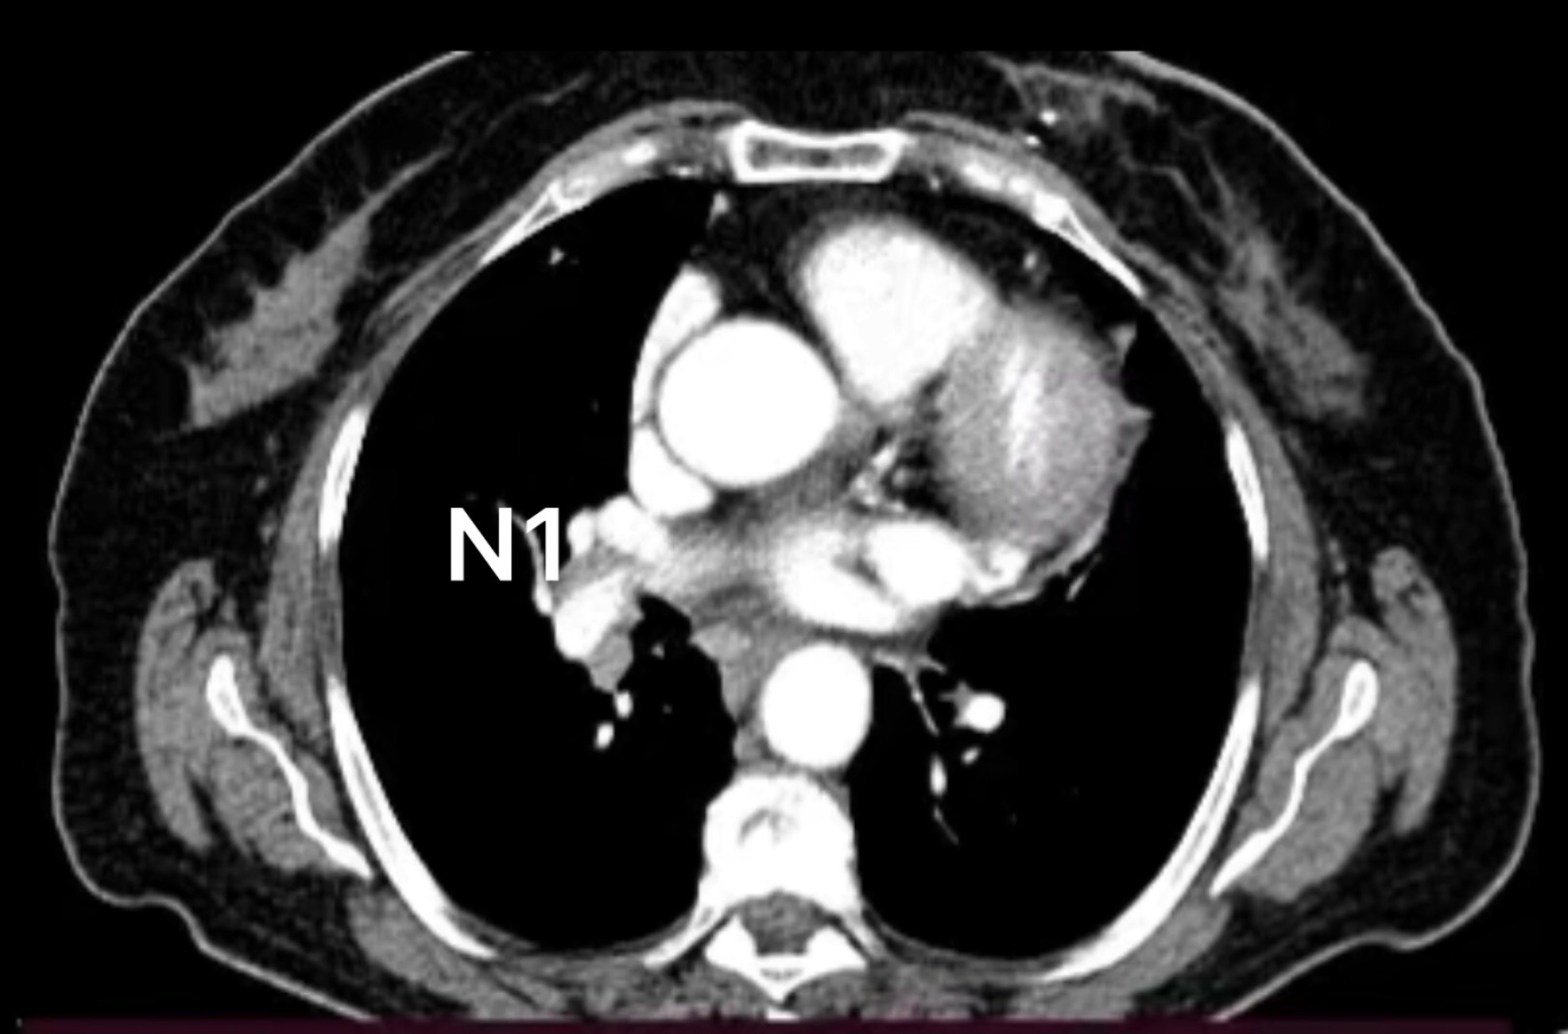

🫁Nel caso in esame una paziente di 74 anni è stata sottoposto ad intervento di lobectomia inferiore destra con asportazione linfonodale mediante tecnica robotica.